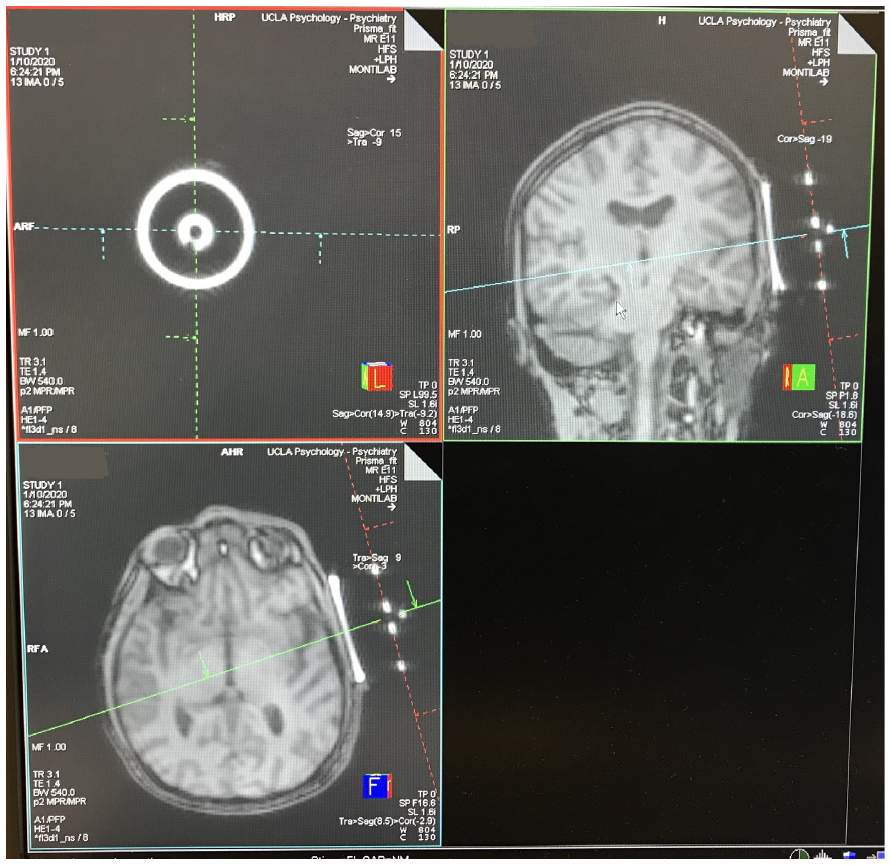

對於任何經顱聚焦超音波(tFUS)系統而言,MR 相容性通常相當複雜,因為換能器含有導電材料。BrainSonix 換能器特別設計內含 MRI 透光定位標記材料,並經驗證可在 3T MRI 環境中安全運作。具體而言,已證實在 128 MHz 頻率下與掃描器射頻發射及接收線圈無交互作用(Korb 2014)。換能器透過 MR 條件相容電纜連接,並經由牆壁濾波器連至刺激器主控台。提供的換能器固定架為 MR 安全設計,可實現簡單且穩固的定位與角度調整。MR 同步透過光纖輸入線及光隔離數位訊號線(TTL)提供,允許同步進行 MRI 擷取。

下方左側圖像顯示換能器定位標記的 MRI 影像。

下方中間圖像顯示對齊過程。

下方右側圖像顯示焦區的大約位置(黃色橢圓)(Schafer 2021)。